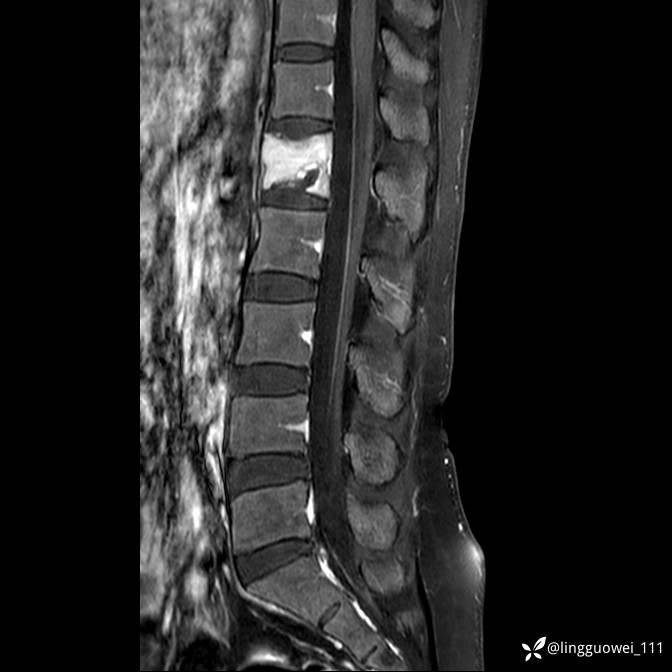

病例女,39岁,腰痛来诊,只有CT可能要鉴别诊断,而MR可以定性吗?

患者性别:女

患者年龄:39岁

主诉:腰痛

T2

T2+FS

T1+C